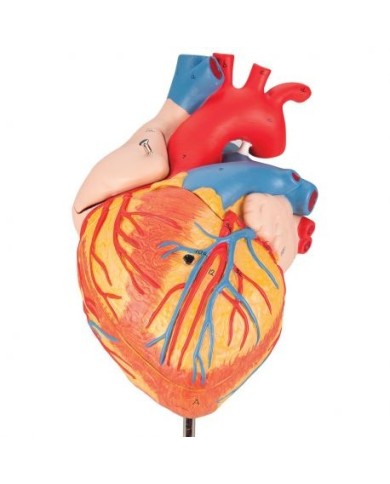

Per una migliore comprensione delle strutture anatomiche del cuore sono stati realizzati anche dei modelli anatomici di cuore ingrandito, si va dai piccoli ingrandimenti fino ai modelli di cuore per la formazione in aula, come il modello anatomico di cuore gigante prodotto da 3B Scientific: un modello di cuore ingrandito di ben otto volte.